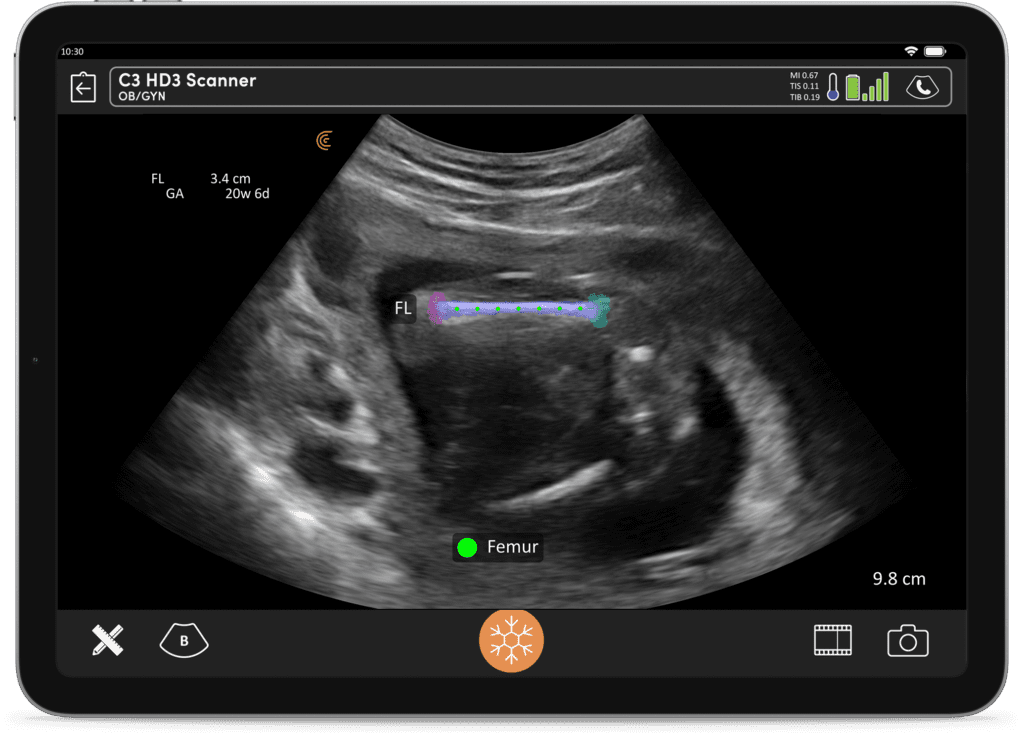

OB AI Clarius